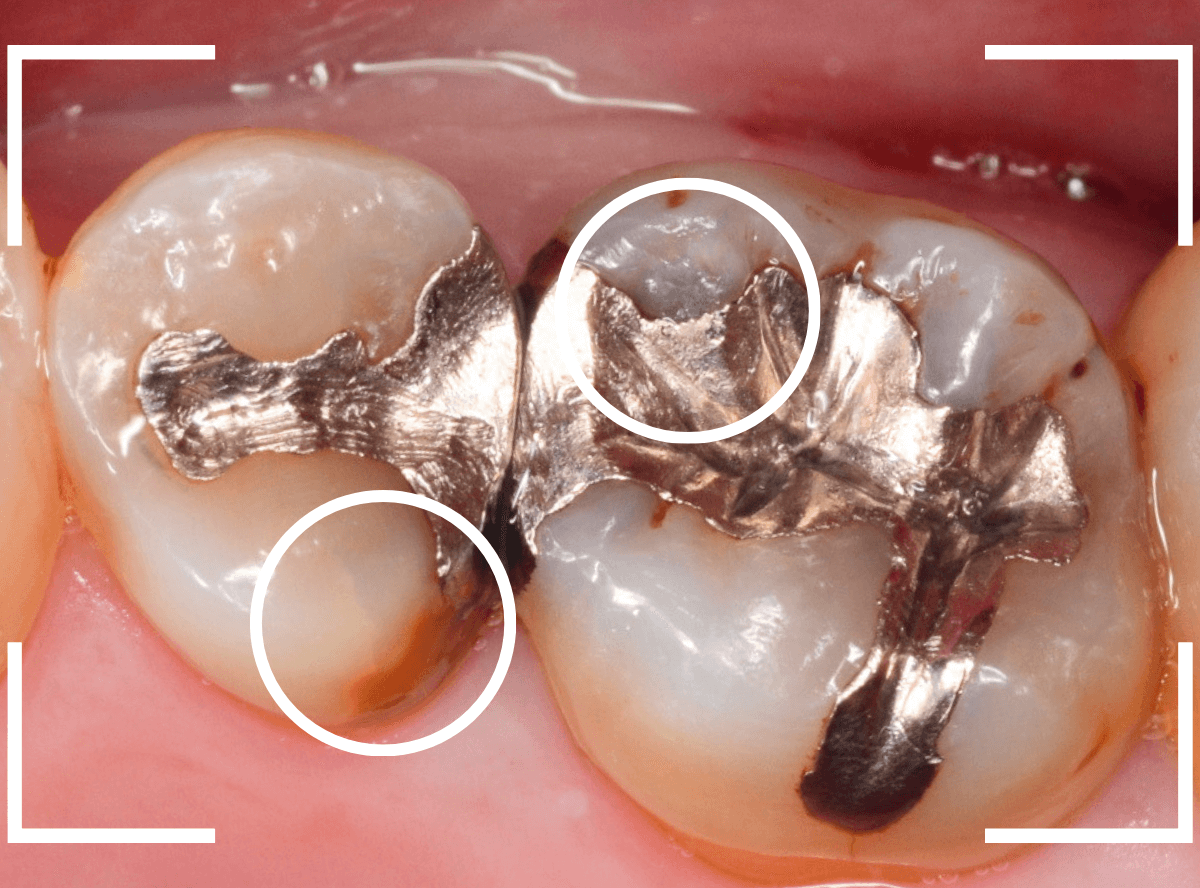

Case.20 メタル・インレーとメタル・クラウンをジルコニアにやり替え

「下の奥歯の銀歯を白くしたい」というご希望の患者さんです。

メタル・インレーとメタル・クラウンが入っていますね。

検査の結果、再製に問題なさそうでしたので、治療を進める事になりました。

まずは、奥のメタル・クラウンを外します。

メタル・コアが入っていますが、こちらも慎重に外して、中を調べていきます。

レントゲン写真では問題なさそうでしたが、メタルコアを除去すると、中は真っ黒でした。

このように、コアの中で虫歯が進行している場合もありますので、さし歯をやり直す際は、出来る限りコアも外して調べるようにしています。